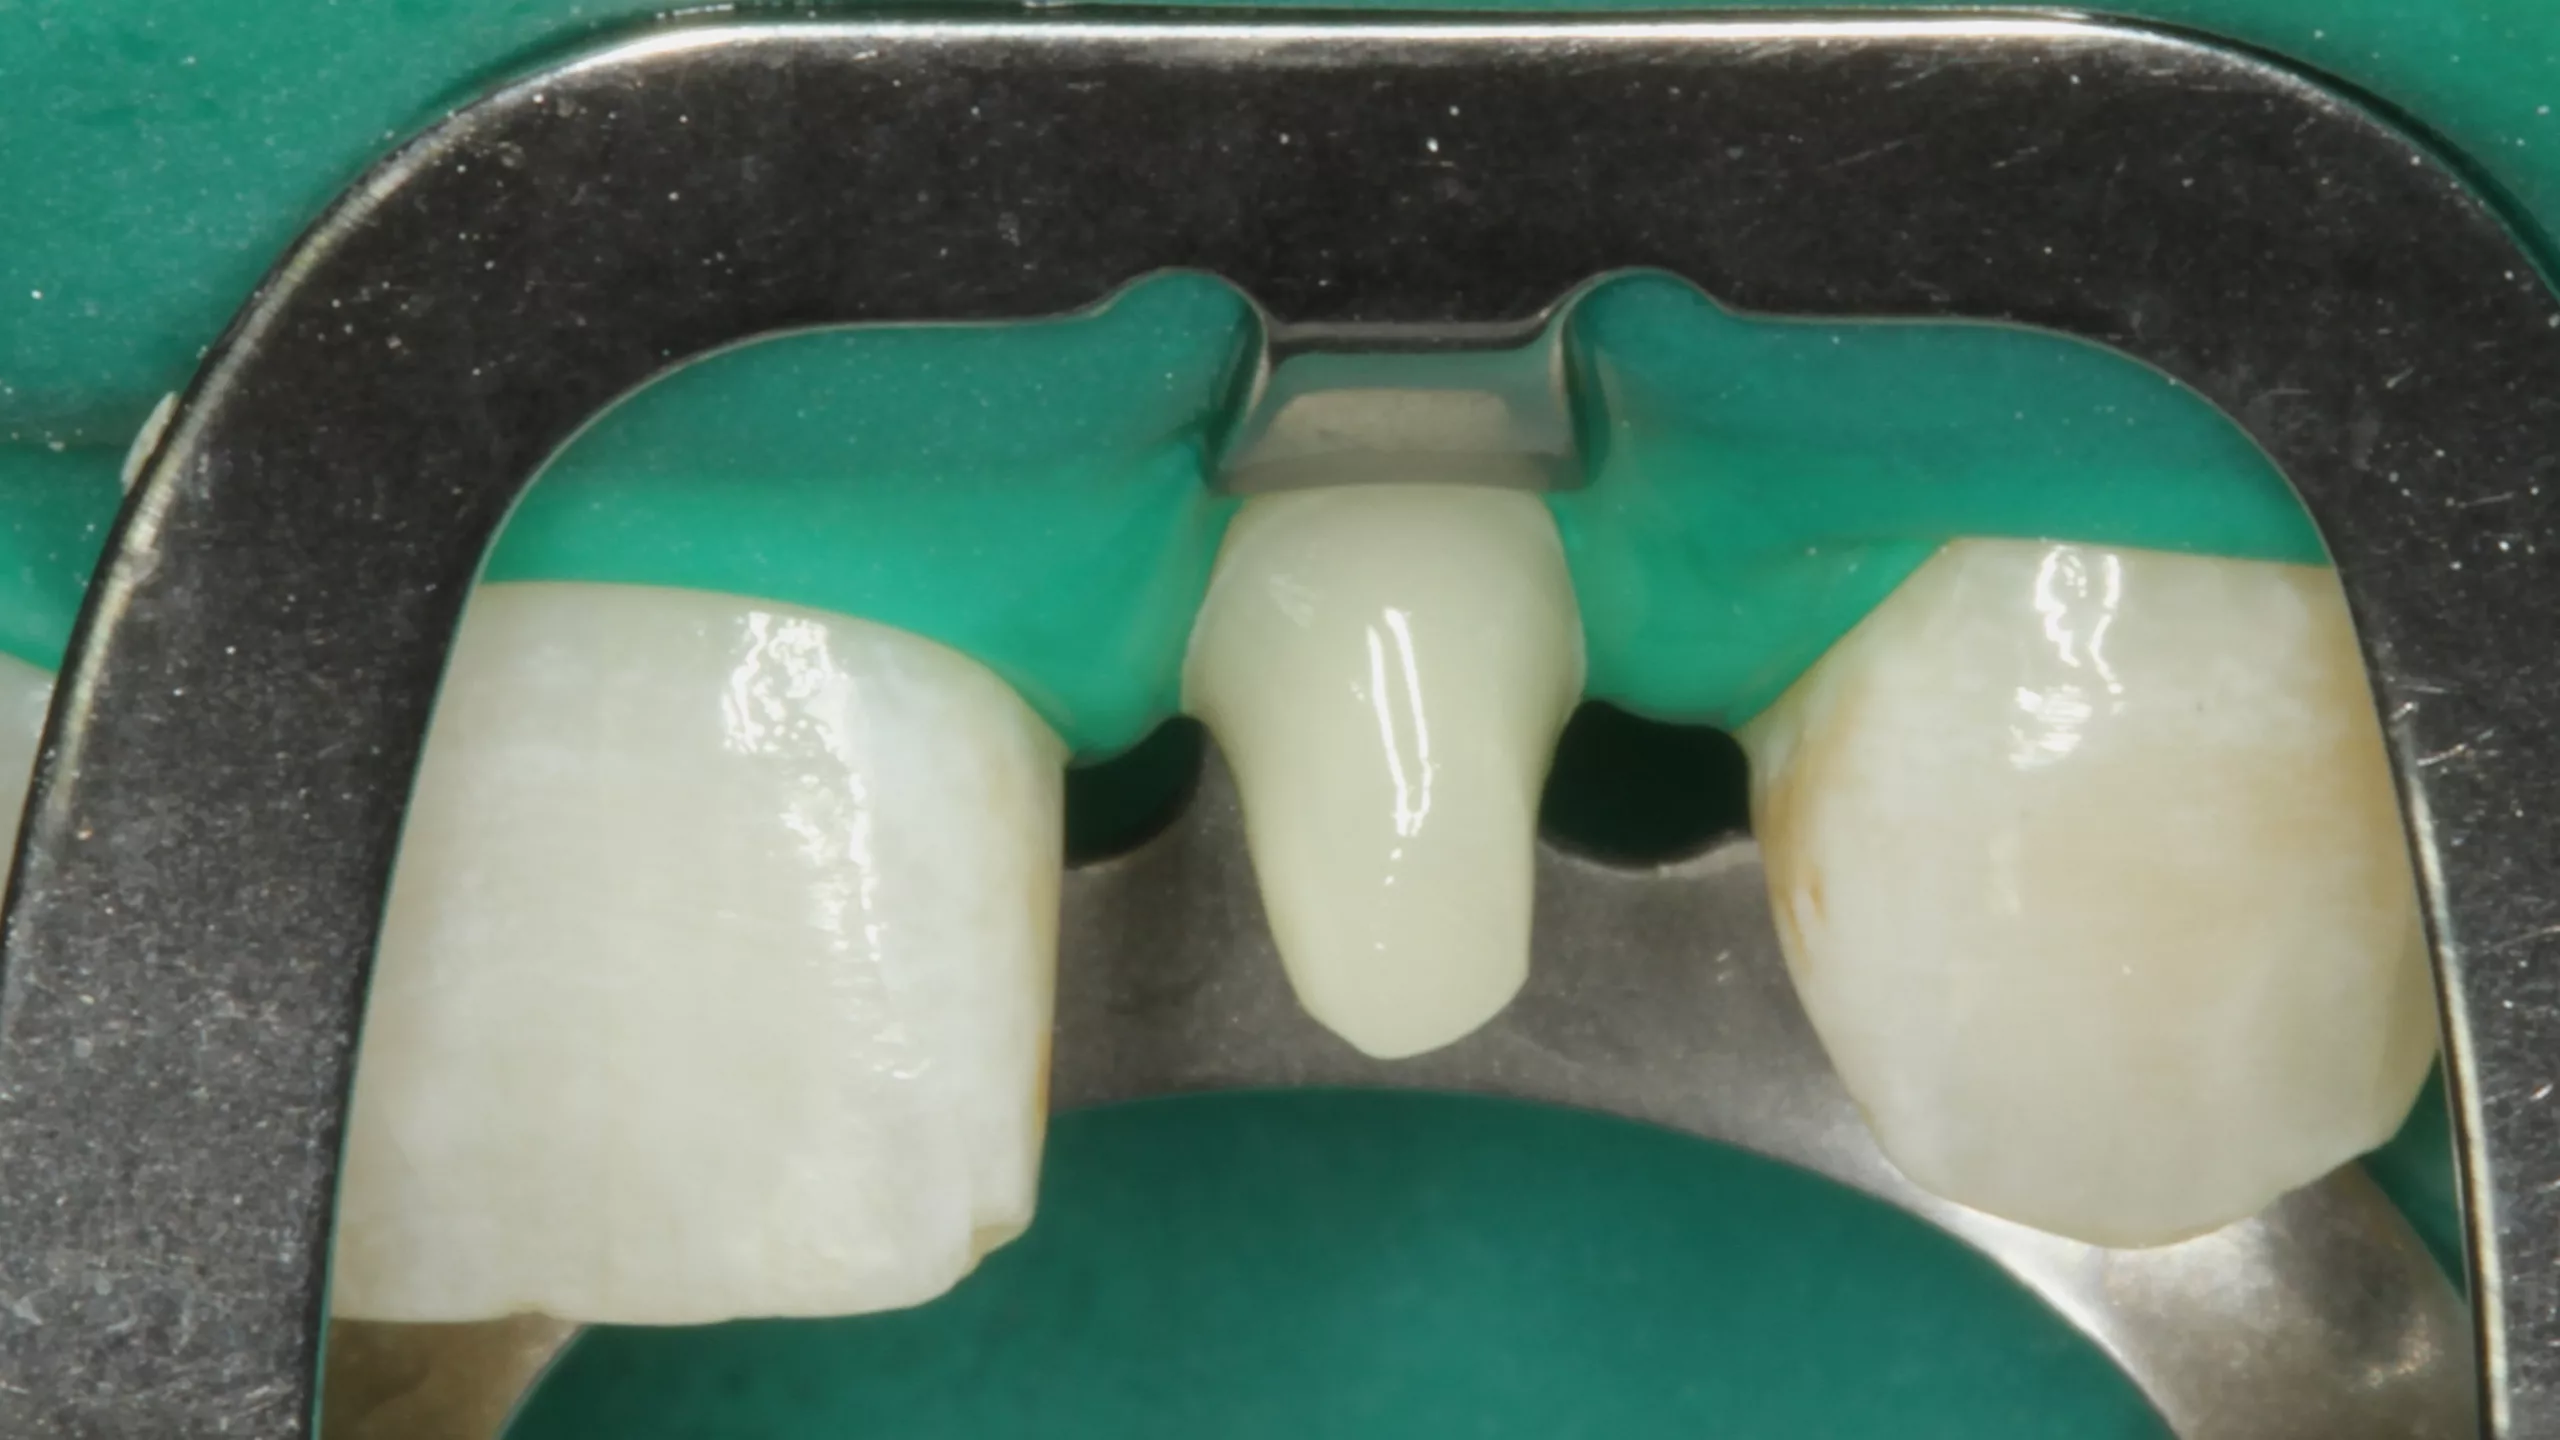

Weiter geht es am Zahn: Die Kontaminationskontrolle ist bei der adhäsiven Befestigung essenziell [84]. Das einfachste Tool – gerade bei adhäsiven Teilkronen – ist die Kofferdamisolierung. Die Abbildung 2 zeigt den isolierten Arbeitsbereich nach Entfernung der Provisorien, der Reinigung der Klebeflächen mit Ultraschall und Bims-Paste (Zircate, Dentsply Sirona) sowie dem Abstrahlen der Kompositfläche an Zahn 46 mit 50 ?m Aluminiumoxid (Rondoflex, KaVo). Die kurze, flügellose Molaren-Kofferdamklammer erleichtert den Zugang zum Approximalraum bei der Versäuberung mit Zahnseide. Da es sich in diesem Bereich um eine adhäsive Kavitätenbodenelevation mit Komposit [66] im Vorfeld der Präparaton und nicht um eine adhäsive Aufbaufüllung handelt, kommt der suffizienten Vorbehandlung auch dieser Klebefläche eine entscheidende Bedeutung zu, um einen Haftverbund zwischen dem Komposit und dem adhäsiven Befestigungssystem zu gewährleisten.

Nach der Schmelzkonditionierung mit dem Phosphorsäuregel und dem ausreichenden Spülen für 15 Sek. ist für eine suffiziente volladhäsive Anbindung ein Benetzungsmittel, ein „Tooth Primer“ erforderlich. Der zu Visalys CemCore gehörende Visalys Tooth Primer ist ein selbstkonditionierender Einkomponenten-Primer, der keiner separaten Lichthärtung bedarf und somit die Ansprüche an die Selbsthärtung des Adhäsivs, die anschließend im Kontakt mit Visalys CemCore abläuft, erfüllt. Die Abbildung 3 zeigt die Einwirkung des Visalys Tooth Primers auf die Präparationsflächen der beiden Zähne 46 und 47. Die Befestigung der Teilkronen erfolgte gleichzeitig mit Visalys CemCore in der Farbe Universal (A2/A3), das vorab direkt auf die Teilkronen und nicht in die Kavitäten appliziert wurde (Abb. 4). Obwohl eine „Tack Cure“-Technik-Option zur Verfügung steht, wurden die Überstände des Befestigungsmaterials mittels Modellierspatel, frischem Bondingpinsel und Zahnseide entfernt. Die im Vergleich zu herkömmlichen Befestigungskompositen etwas höhere Konsistenz und bessere Standfestigkeit (kommt primär der Funktion als Stumpfaufbaukomposit zugute) erleichtert die Überschussentfernung immens, da das Material nicht so schnell unkontrolliert wegfließt. Es erfolgte eine initiale Härtung mittels eines Hochleistungs-LED-Polymerisationsgerätes. Zur Verhinderung der Sauerstoffinhibitionsschicht kann jedes herkömmliche Glyceringel verwendet werden. Alternativ kann die ebenfalls von Kettenbach angebotene Visalys CemCore Try In-Paste zur Anwendung kommen. Obwohl Visalys CemCore eine ausgezeichnete Selbsthärtung aufweist, erfolgte dennoch eine Lichthärtung unter Glyceringel für 20 Sek. pro Fläche. Die Überprüfung der statischen und dynamischen Okklusion darf erst nach Abschluss der Dunkelhärtung vorgenommen werden, damit die adhäsive Integration nicht gestört wird, wenn im Polymerisationsprozess durch Exkursionsbewegungen mechanisch auf die Klebefläche eingewirkt wird.